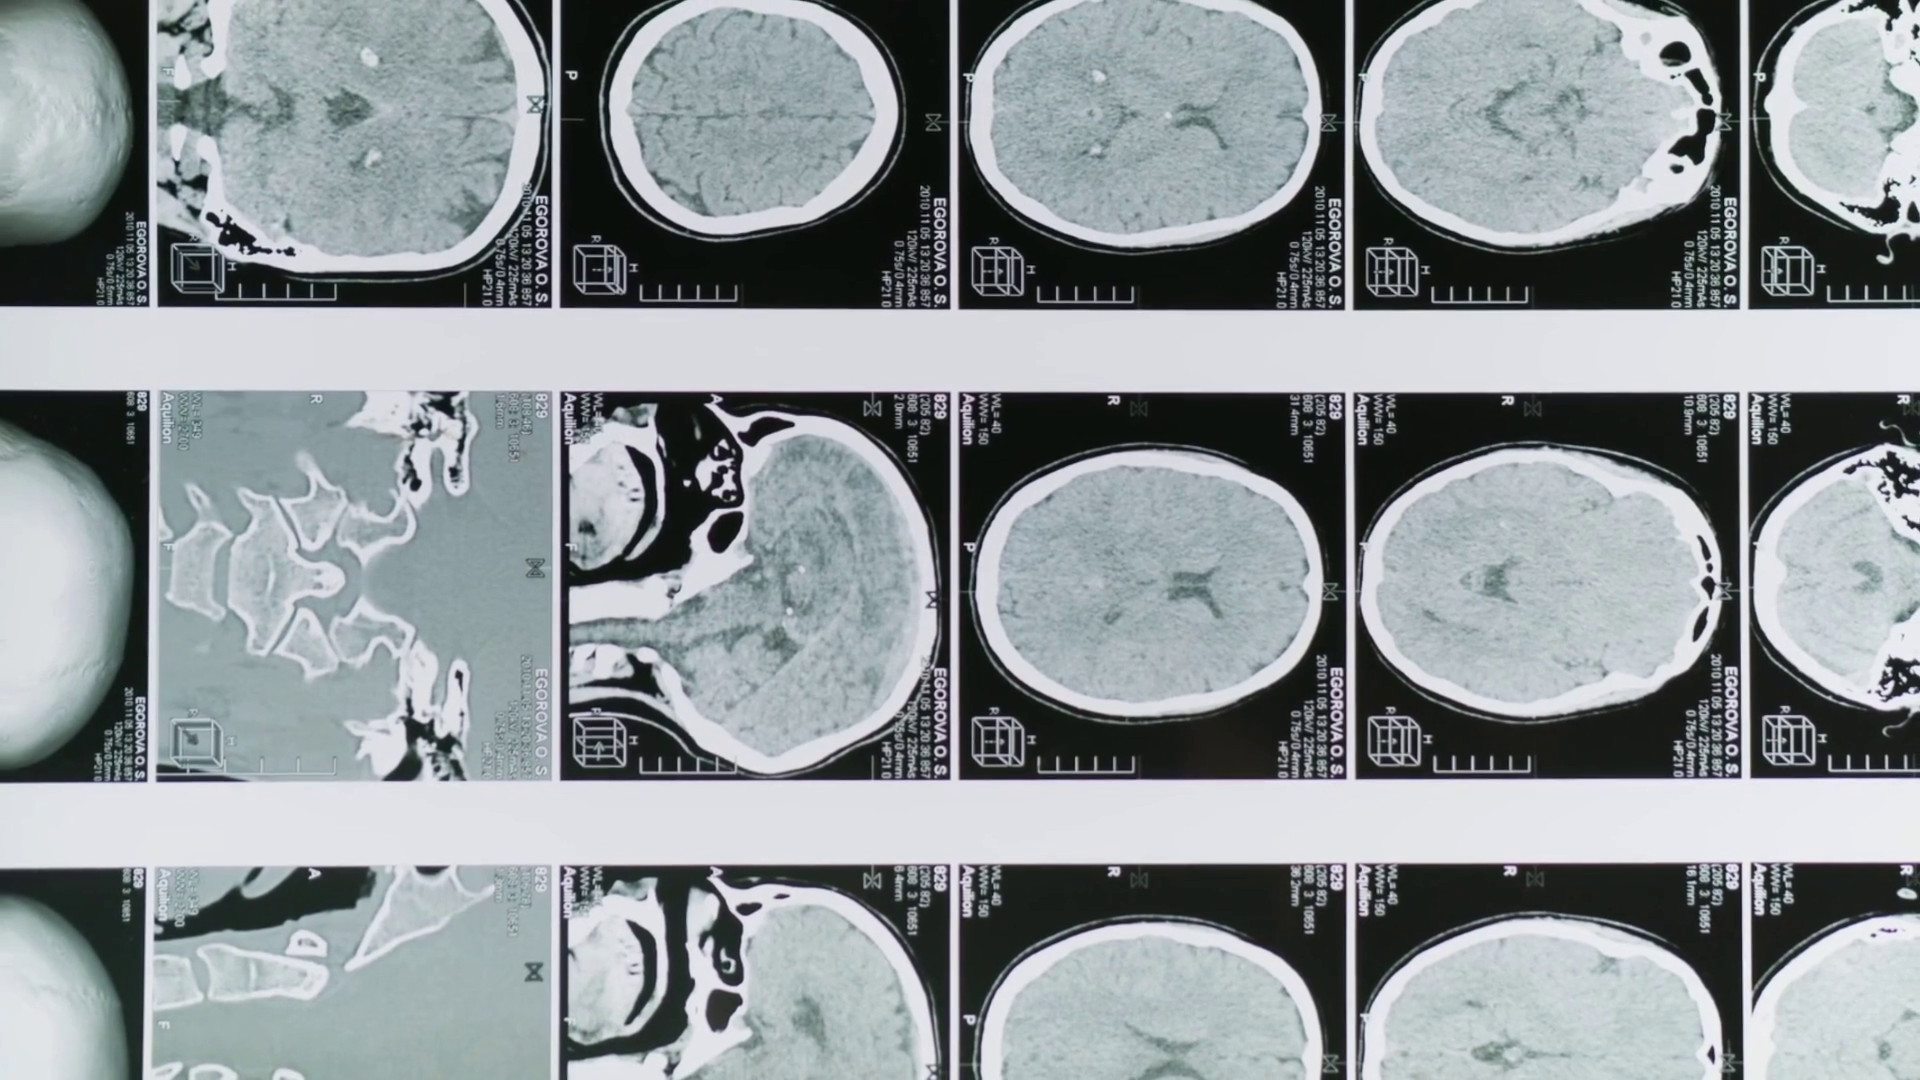

Glioblastoma, le molecole naturali migliorano la chemioterapia

Glioblastoma, le molecole naturali migliorano la chemioterapia

Glioblastoma, le molecole naturali migliorano la chemioterapia